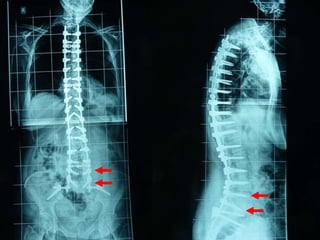

Εκφυλιστική κύφωση – σκολίωση ενήλικος

(+) Parkinson

Προσθία προσπέλαση

Autografts

Οπίσθια προσπέλαση